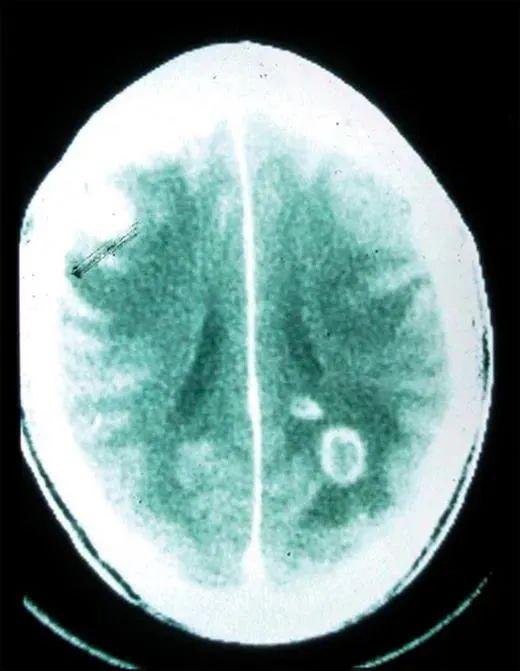

弓形蟲感染人類大腦丨Sullivan & Jeffers, 2012

人體內原本存在一些屏障,將人體重要部位與身體其他部分的內環境分割開來,防止病原體的入侵,但弓形蟲卻能夠跨越這些屏障。例如,它們就能跨越血胎屏障,這就是爲何如果孕婦感染了弓形蟲,可能對胎兒造成嚴重的影響,嚴重時甚至可能導致流產;它們也能跨越血腦屏障,並引起各種中樞神經病症,比如癲癇等。當然,它們也能跨越血睾屏障,對男性的生殖系統產生影響。